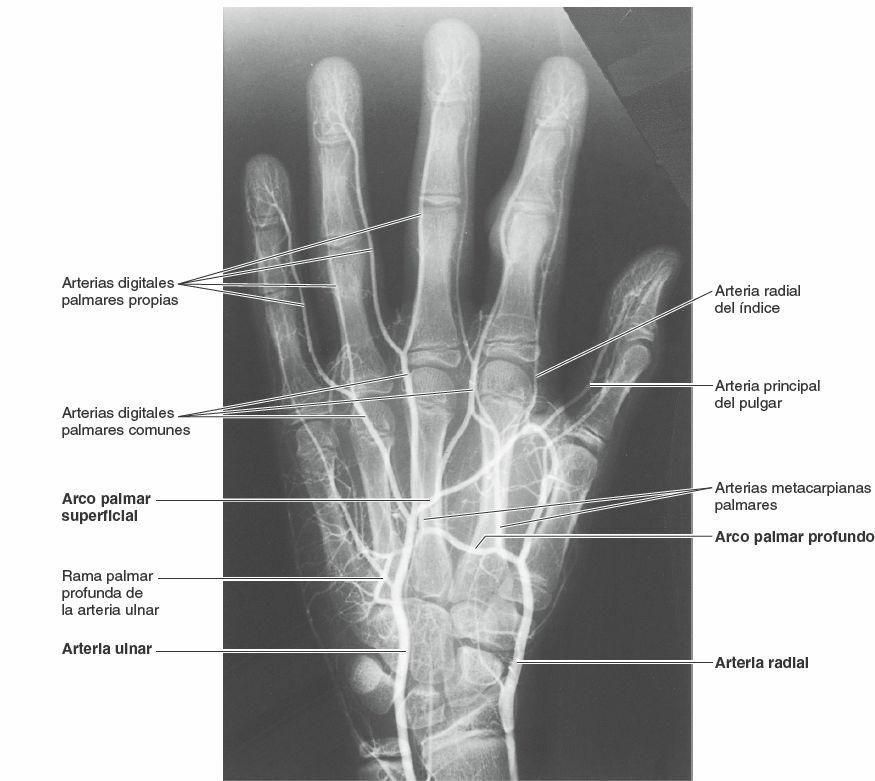

Arterias de la mano

Las funciones de la mano requieren que esta se sitúe y mantenga en numerosas posiciones distintas, con frecuencia mientras agarra o aplica presión, y por ello está dotada de numerosas arterias profusamente ramificadas y anastomosadas para que todas sus partes dispongan en general de sangre oxigenada en todas las posiciones.

Además, las arterias y sus ramificaciones son relativamente superficiales y se encuentran por debajo de una piel capaz de sudar, característica que permite la disipación del exceso de calor. Para evitar una pérdida indeseable de calor en un entorno frío, las arteriolas de las manos pueden reducir su flujo sanguíneo en la superficie y en las puntas de los dedos. Las arterias ulnar y radial y sus ramas proporcionan toda la sangre que va a la mano. Las arterias de la mano se ilustran en las figuras 3-82 y 3-83, y sus orígenes y recorridos se describen en la tabla 3-15.

La arteria ulnar entra en la mano anterior al retináculo de los músculos flexores entre el pisiforme y el gancho del ganchoso, y a través del conducto ulnar (de Guyon) (fig. 3-70 B). La arteria ulnar discurre lateralmente al nervio ulnar (fig. 3-77 A). Se divide en dos ramas terminales: el arco palmar superficial y el arco palmar profundo (figs. 3-82 y figs. 3-83). El arco palmar superficial (terminación principal de la arteria ulnar) da origen a tres arterias digitales palmares comunes que se anastomosan con las arterias metacarpianas palmares procedentes del arco palmar profundo. Cada arteria digital palmar común se divide en un par de arterias digitales palmares propias, que discurren a lo largo de los lados adyacentes de los dedos 2º a 4º.

Arteria radial

La arteria radial se curva dorsalmente alrededor del escafoides y el trapecio, y cruza el suelo de la tabaquera anatómica (fig. 3-65). Entra en la palma entre las cabezas del primer músculo interóseo dorsal y a continuación gira medialmente para pasar entre las cabezas del aductor del pulgar. La arteria radial termina cuando se anastomosa con la rama profunda de la arteria ulnar para formar el arco palmar profundo, que depende principalmente de la arteria radial. Este arco cruza los metacarpianos justo distalmente a sus bases (fig. 3-79). El arco palmar profundo da origen a tres arterias metacarpianas palmares y a la arteria principal del pulgar (figs. 3-82 y 3-83). La arteria radial del índice pasa a lo largo de la cara lateral del dedo índice; normalmente se origina de la arteria radial, pero también puede hacerlo de la principal del pulgar.